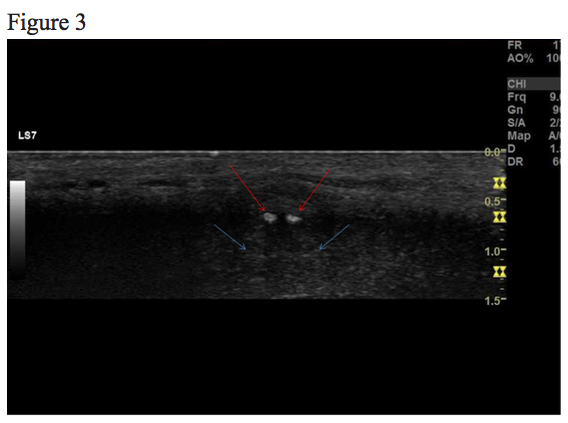

Figure 1, 2, 3 and 4 show the same hypoechoic lesion, a Peyronie’s plaque, in the penile connective tissue. The lesion has a well-defined circumference.

Figure 4. Elastography image shows that the lesion is harder relative to the surrounding tissue.